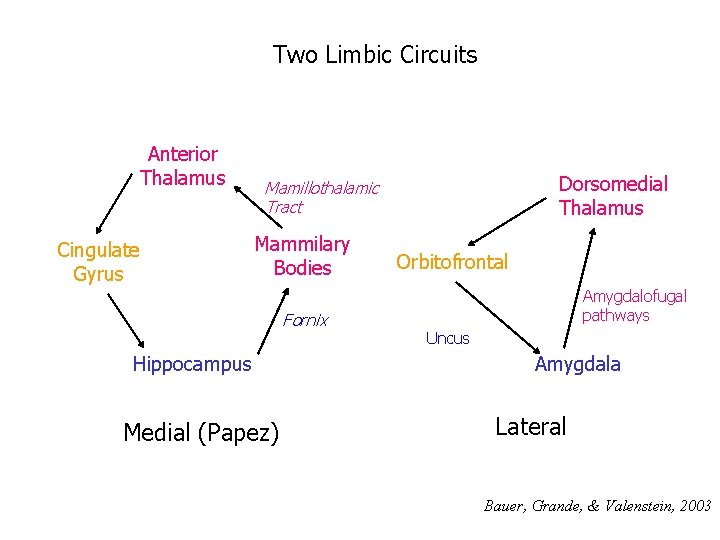

Two Limbic Circuits Anterior Thalamus Cingulate Gyrus Dorsomedial Thalamus Mamillothalamic Tract Mammilary Bodies Fornix Hippocampus Medial (Papez) Orbitofrontal Amygdalofugal pathways Uncus Amygdala Lateral

Two Limbic Circuits and the Two-system theory of amnesia Anterior Thalamus Cingulate Gyrus Dorsomedial Thalamus Mamillothalamic Tract Mammilary Bodies Orbitofrontal Amygdalofugal pathways Fornix Uncus Hippocampus Amygdala PRPH Medial (Papez) Lateral

Two Limbic Circuits and the Two-system theory of amnesia Anterior Thalamus Cingulate Gyrus Dorsomedial Thalamus Mamillothalamic Tract Mammilary Bodies Fornix Hippocampus Medial (Papez) Orbitofrontal Amygdalofugal pathways Uncus Amygdala Lateral

Two Limbic Circuits Anterior Thalamus Cingulate Gyrus Dorsomedial Thalamus Mamillothalamic Tract Mammilary Bodies Fornix Hippocampus Medial (Papez) Orbitofrontal Amygdalofugal pathways Uncus Amygdala Lateral

Two Limbic Circuits Anterior Thalamus Cingulate Gyrus Dorsomedial Thalamus Mamillothalamic Tract Mammilary Bodies Fornix Hippocampus Medial (Papez) Orbitofrontal Amygdalofugal pathways Uncus Amygdala Lateral Bauer, Grande, & Valenstein, 2003